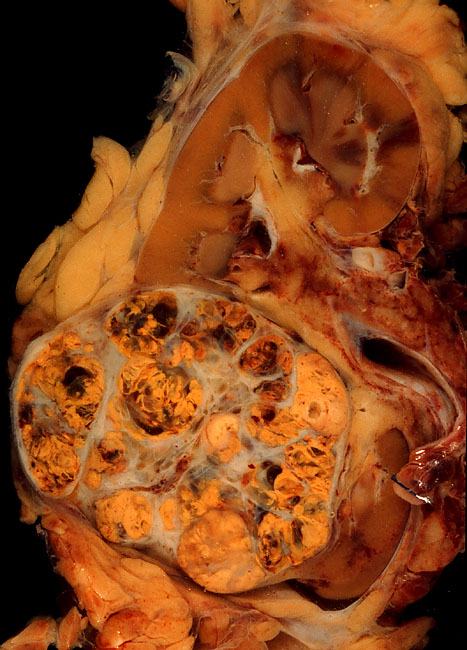

Hay una mayor incidencia de la enfermedad quística adquirida del riñón en pacientes sometidos a largo plazo la diálisis renal, lo que predispone al cáncer de células renales. La esclerosis tuberosa

El trasplante renal: Adquisición de la enfermedad quística renal del riñón nativo también predispone al cáncer de células renales en receptores de trasplante renal.